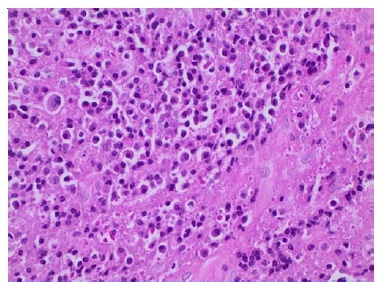

Além disso, não foi diagnosticada lesão mandibular no primeiro episódio. A paciente comunicou que omitiu o diagnóstico durante a anamnese por não acreditar ter relação com a odontalgia, e por ter feito exames laboratoriais e de imagem de corpo inteiro que descartaram qualquer sinal do mieloma, há cerca de trinta dias. Realizou-se punção aspirativa por agulha fina da área entumecida, não sendo observado presença de material líquido, sendo então optado pela realização de biopsia incisional (Figura 4), sob anestesia local, devido a necessidade de conclusão do diagnóstico. Durante o procedimento cirúrgico foi possível evidenciar um nódulo de superfície lisa, brilhante, avermelhada com estrias esbranquiçadas e friável a manipulação. A análise histopatológica (Figuras 5, 6 e 7), corada com Hematoxilina e Eosina, revelou proliferação de células de morfologia plasmocitóide, que apresentavam atipia, cromatina nuclear pontilhada e invasão do tecido conjuntivo, conferindo o laudo de mieloma múltiplo, sem necessidade de marcação imunohistoquímica, devido ao diagnóstico dessa lesão no passado.

Figura 6 Denso infiltrado de plasmocitos com núcleo grande e excentrico, nucleolo proeminente, moderado citoplasma e presenca de atipia (x200 - coloracao com Hematoxilina e Eosina)